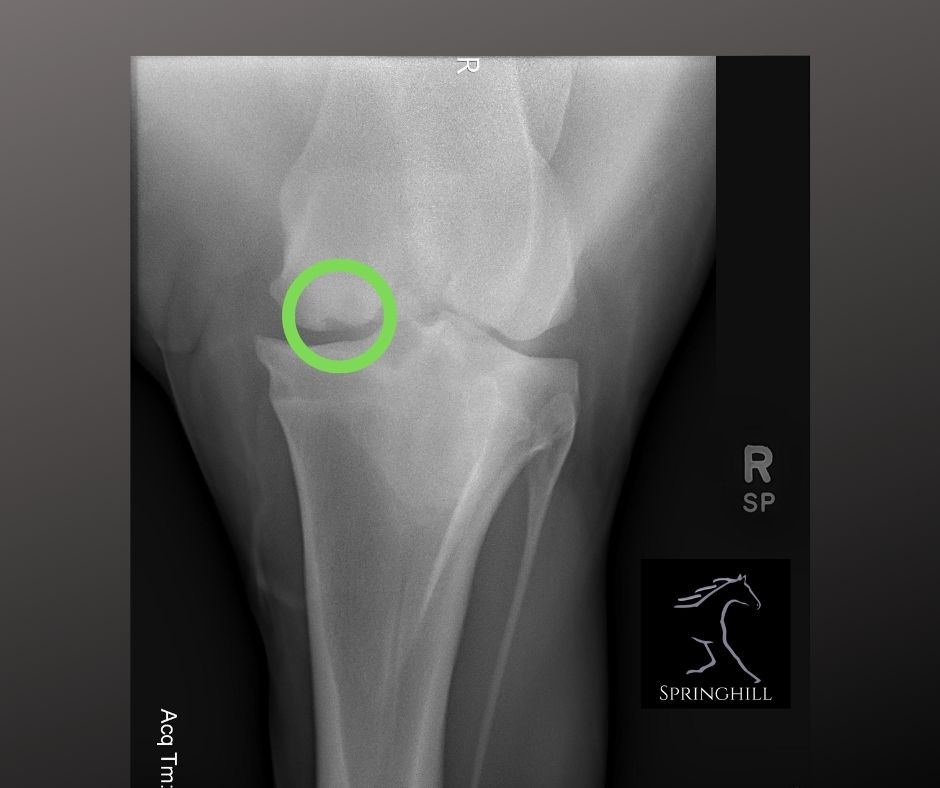

From springhillequine.com

OCD in Horses Springhill Equine Veterinary Clinic How Much Is An X Ray For A Horse I paid right around $200 for lateral and sunrise views on both fronts in the local. Combined with ultrasound examination, or even ct and. Radiography is a commonly used imaging modality in horses, particularly in the event of a sale or lameness diagnosis: “digital x rays probably run between $50 and $60 per view for a particular site,” mark reilly,. How Much Is An X Ray For A Horse.